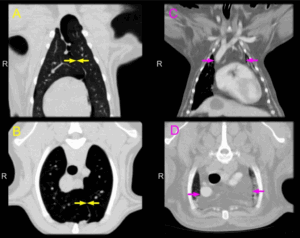

Увеличение тех, которые находятся в труднодоступных местах, можно диагностировать с помощью компьютерной или магнитно-резонансной томографии , ультразвукового исследование. Также всегда назначается общий анализ крови и мочи.

- Магнитно-резонансная или компьютерная томография.

При углубленном обследовании пациента с ЛАП возникает необходимость в использовании дополнительных инструментальных и лабораторных методов исследования. Одним из них является ультразвуковое исследование (УЗИ) ЛУ, которое позволяет уточнить их размеры, определить давность патологического процесса и его остроту. При остром воспалении определяется гипоэхогенность и однородность ЛУ. Спаянные ЛУ позволяют предположить продолжительность заболевания более 2 мес. При хроническом течении процесса эхогенность ЛУ повышается.